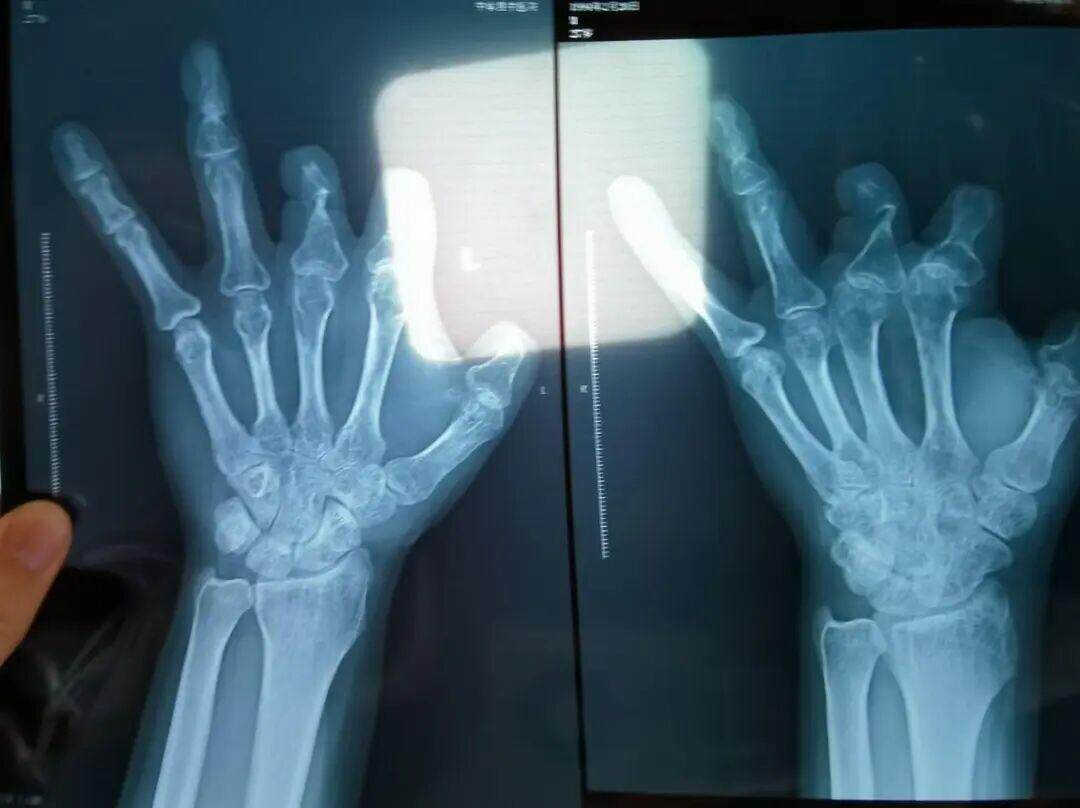

单价1.68万元,声称在术中植入体内、用于缝合血管的两个环形吻合装置,竟然在王海森的X光片上消失了。

装置上带有不锈钢针,不可能被人体吸收,唯一的可能就是“手术时其实没有使用”。尽管之前也有其他人向王海森透露过这一点,但直到看到片子前,他一直都不相信。

彭先生称,因为他的手术并不成功,术后他委托律师欲将郑大一附院诉至法庭。在律师的指导下,他到医院拍摄了X光片,偶然发现术中使用的6个吻合装置,都“消失”在了血管内。

该产品的代理商曾向新京报记者证实,微血管吻合装置为植入型医疗器材,患者拍摄X光片时会有显示。新京报记者获取了一位曾在郑大一附院接受手术、使用了该产品的患者的X光片,其手术部位可见一绿豆大小的光圈。

王海森称,他出院约1年后,有人曾找到他说,这个价格昂贵的进口器材,并没有在手术中使用。当时他没有相信,直到2021年12月,经人提醒,王海森在老家开封尉氏县人民医院拍摄了左手X光片,才确认手术部位的确没有微血管吻合装置。2021年12月底,王海森向郑州市公安局二七分局刑侦大队报案。

法院判定,多名被害人证明,其术后接受X光检查,体内均无该装置。94名被害人中,有多名1岁、5岁、6岁不等的儿童因手指创伤接受微血管吻合装置治疗,相比成人血管粗细程度,更能证明该治疗行为的虚假性。在手术过程中,王福建明知多名患者不符合使用微血管吻合装置的条件,又隐瞒未实际使用的事实,将该医疗器械的费用,计入患者的收费清单,致被害人超额支付医疗费用。